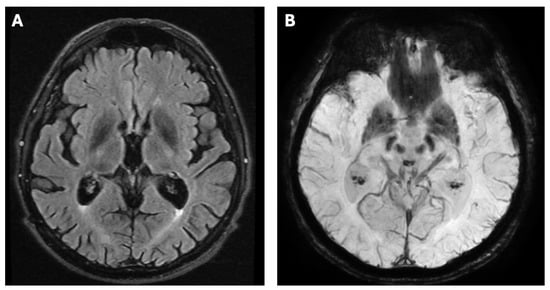

2. Case Report